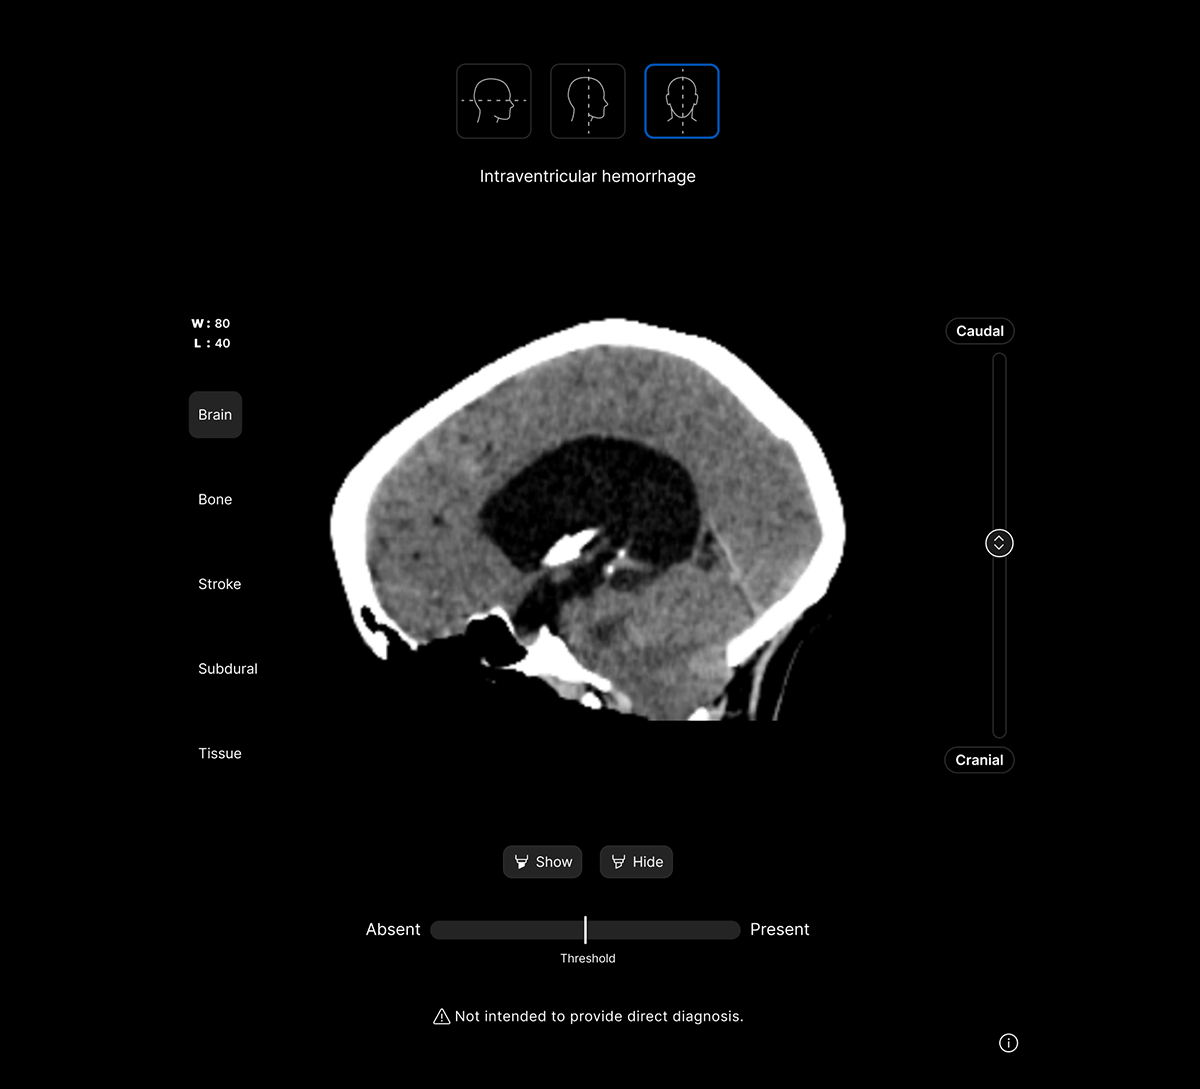

Harrison.ai CT Brain (CTB) is our comprehensive imaging AI solution for non-contrast head CT studies that detects up to 130 findings in under 90 seconds, boosting emergent and incidental capture while surfacing urgent cases for review first – all within the workflow you’re used to.

Let AI find the urgent needles in the non-urgent haystack.

Assist critical decision-making when every minute matters.

Support clinicians providing out-of-hours care.

Maximise clinical value and simplify your workflow with a single comprehensive solution for non-contrast head CT studies, identifying up to 130 findings. No need to juggle multiple solutions for different findings.